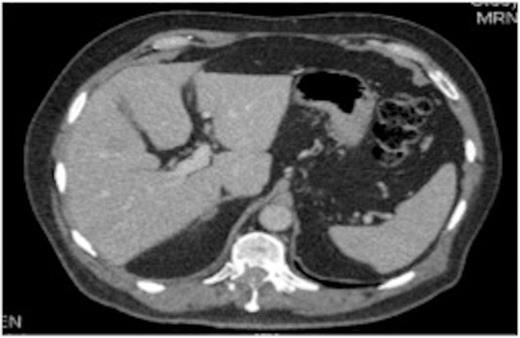

A 63-year-old man presenting with right upper quadrant pain was, following a CT of the chest, abdomen and pelvis, found to have a lesion in the lung and multiple liver metastases.

A liver biopsy was performed. Histological examination showed a low-grade neuroendocrine “carcinoid” tumour, most probably of lung origin.

Original thoracic CT scan, which was performed 2 months prior to the MRI, shows the spinal metastasis

On review of the original thoracic CT scan, which was performed 2 months prior to the MRI, the tumour was distinguishable but, as the spine is such a rare location for carcinoid metastasis, it was initially unreported.